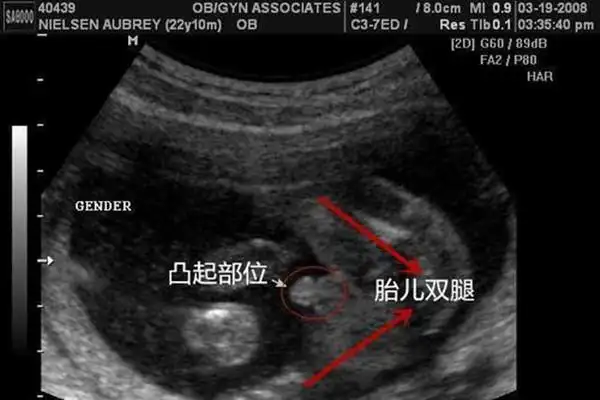

怀孕三个月男胎儿图:准妈妈学会看b超知男女性别

胎儿男女的重要,但这两者的差值尺寸又和父母的个子和重量相关假如